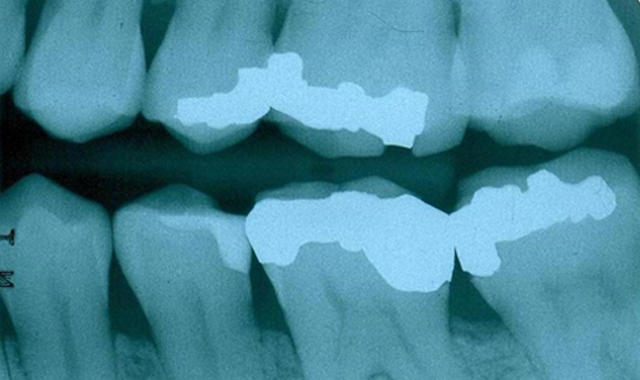

Fig. 1

In this clinical situation, the patient had been complaining of pain on the maxillary left side. Visually, the restorations appeared worn but the margins were intact (Fig. 1). A bitewing radiography did not reveal any radiolucency around the restorations on the teeth (Fig. 2).